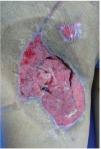

Figura 2 Paciente masculino de 23 años de edad con herida por arma de fuego en miembro pélvico derecho

Figura 3 Mismo paciente manejado con desbridamiento quirurgico, terapia V.A.C.® durante 2 semanas y posteriormente aplicación de Alloderm®

Figura 4 Mismo paciente a los 2 meses del tratamiento.